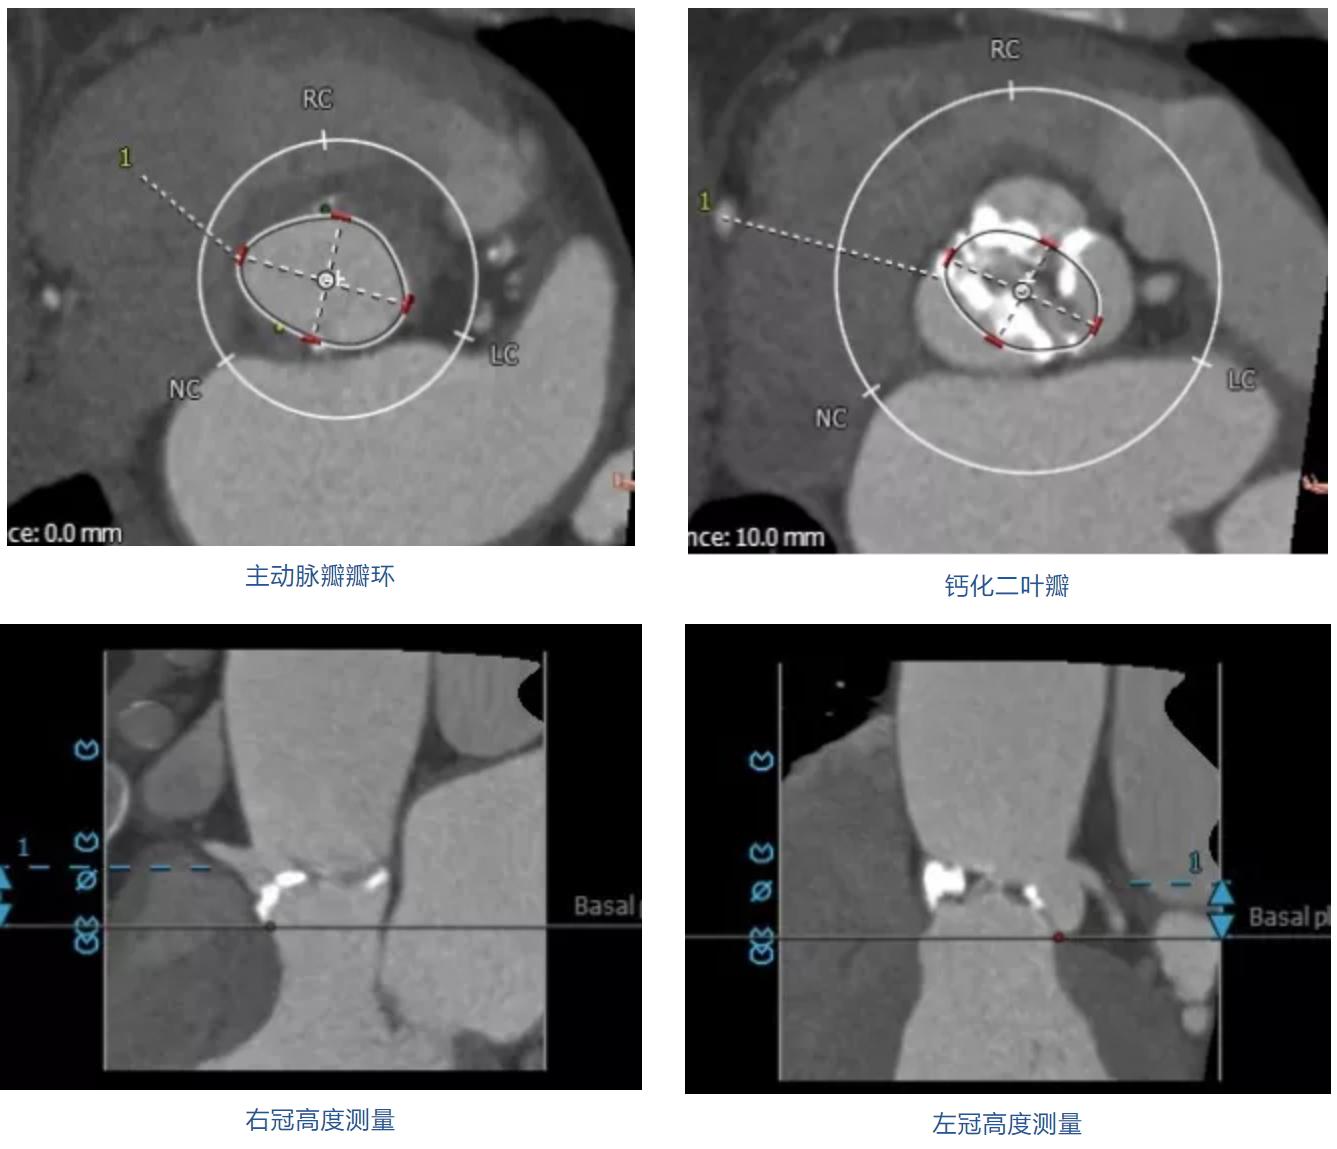

患者男性,79岁,因“活动后胸闷、气促2年,加重1月”入院,术前心脏超声提示主动脉瓣重度狭窄并轻度关闭不全,主动脉瓣二瓣化畸形,明显钙化。患者心功能差,伴冠心病等多种合并症,STS评分19.8%,属于常规外科手术极高风险病例。CT评估结果显示主动脉瓣重度钙化,Type1型二叶瓣,左右融合,瓣环平均直径26.3mm,瓣环面积543.4mm²。左冠脉开口高度12.5mm,右冠脉开口高度13.4mm,外周血管评估提示股动脉血管条件良好,拟行经股动脉TAVI手术。